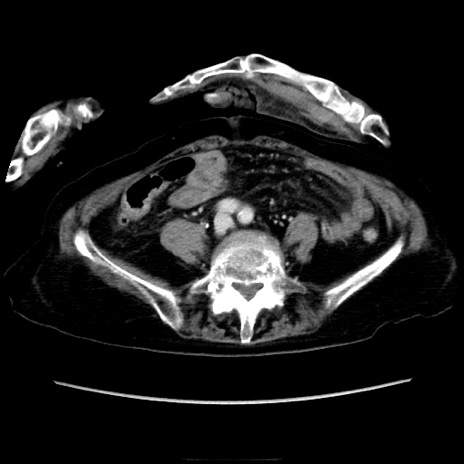

症例40(横断像)

横断像